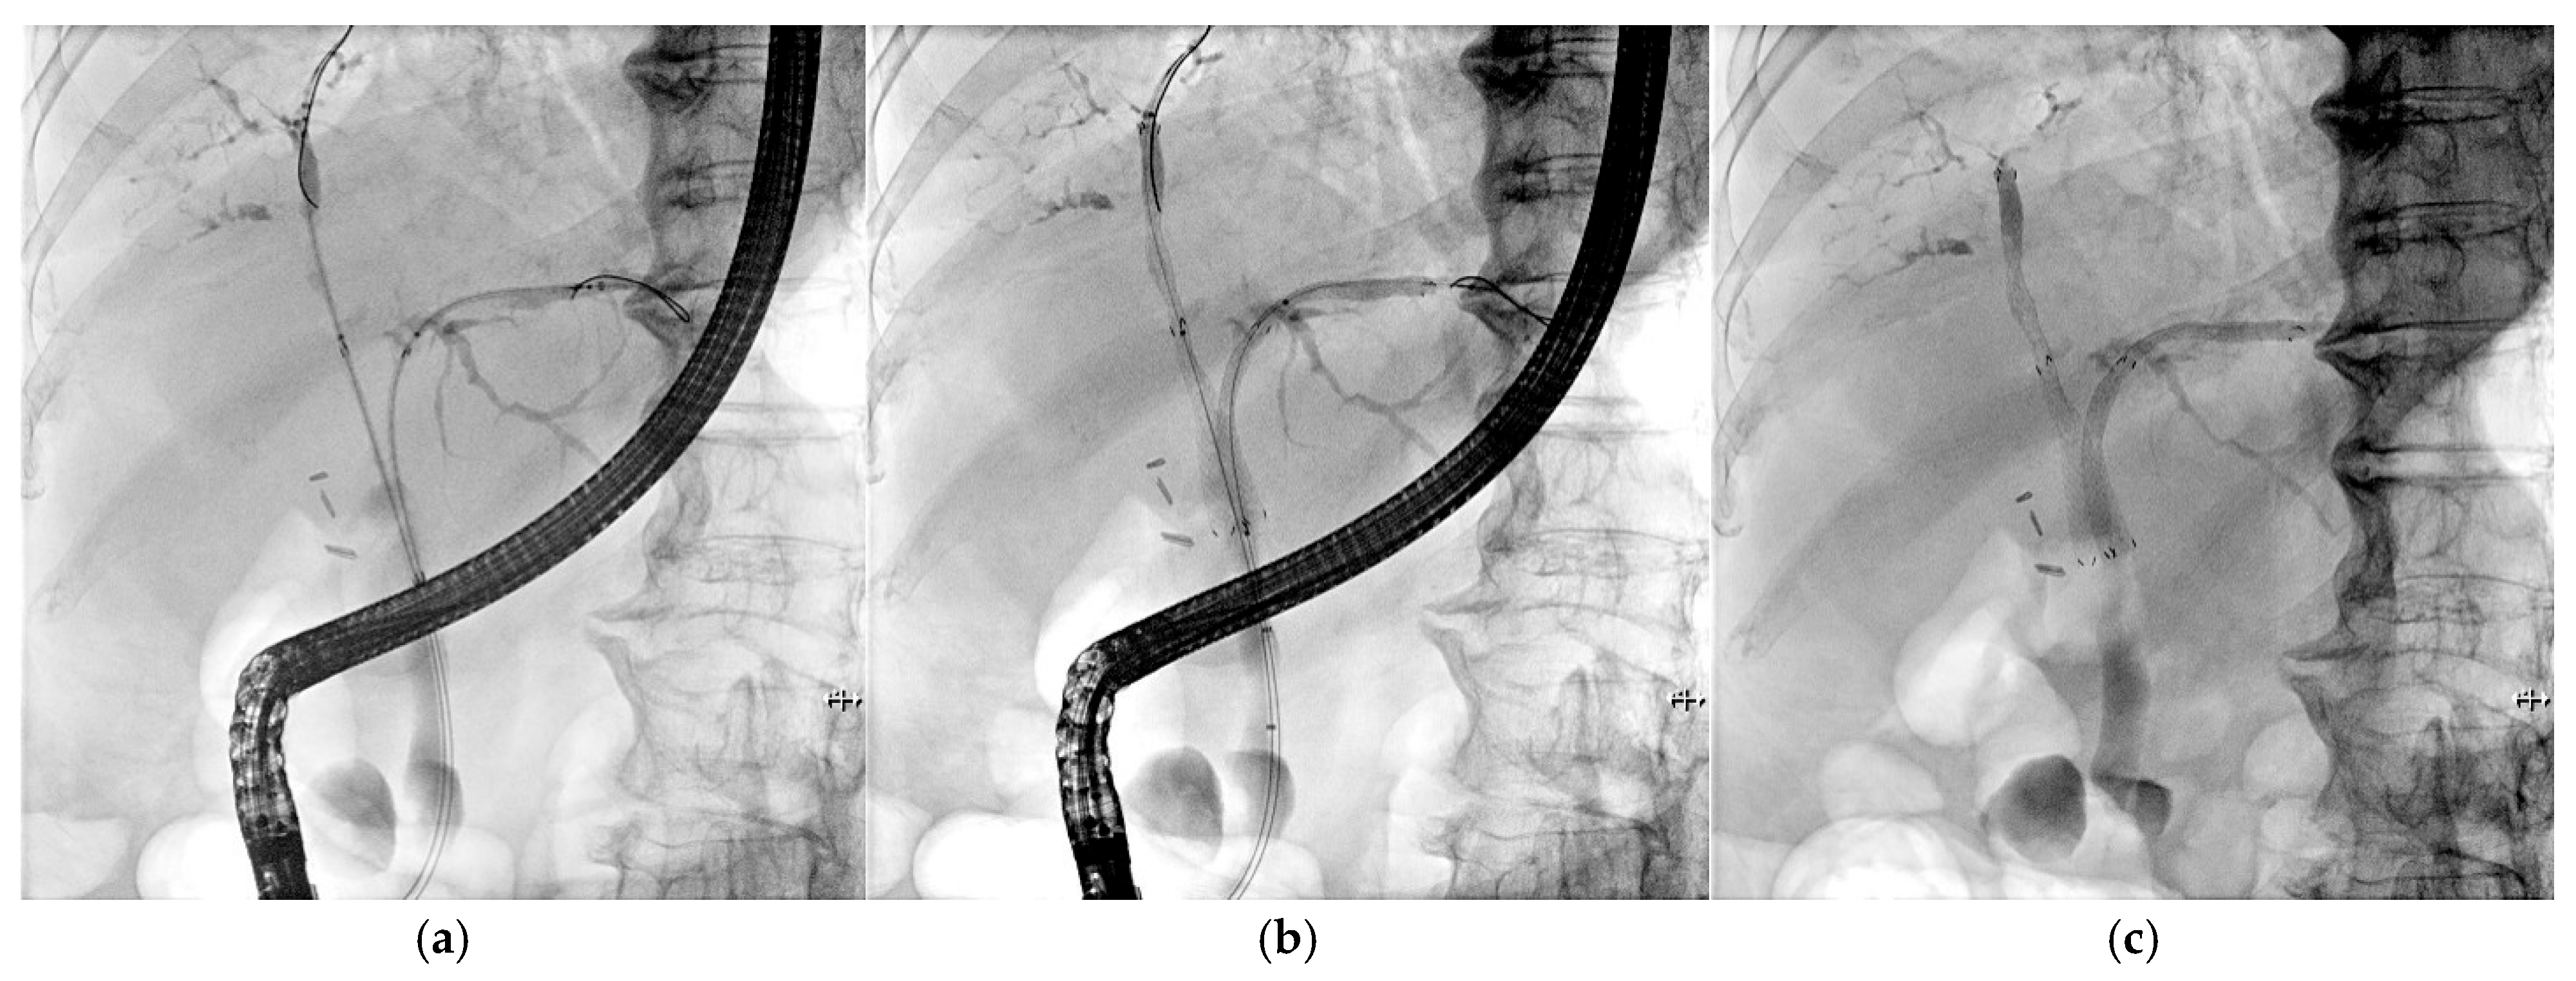

Among the 31 patients with malignant hilar obstruction who underwent simultaneous bilateral stenting, four patients who were transferred to other institutions for supportive care were excluded from the final analysis. Thus, 27 patients were evaluated. Pathological confirmation of malignancy was obtained in all cases, except for 2 patients wherein hilar cholangiocarcinoma was diagnosed based solely on imaging findings and clinical courses. The median age of the study cohort, comprising 16 males and 11 females, was 76 years (range, 52–92 years). The underlying malignancies were hilar cholangiocarcinoma, carcinoma of the gallbladder, and metastatic disease in 20 patients (74.1%), five (18.5%), and two (7.4%) patients, respectively. Two patients were diagnosed with colorectal cancer and hepatocellular carcinoma (n = 1 each). According to the Bismuth classification, 10 (37.0%), 1 (3.7%), and 16 (59.3%) lesions were types II, III, and IV, respectively. The pre-procedure laboratory tests revealed that the median alkaline phosphatase (ALP) and bilirubin levels were 328 IU/dL (range: 98–1489) and 4.9 mg/dL (range: 0.3–25.6), respectively. Post-stent placement chemotherapy was commenced in 19 of the 27 patients (70.4%). Table 1 presents the detailed baseline characteristics of the patients. Figure 2 presents the BenefitTM stent inserted into the patient.

Figure 2. The BenefitTM stent inserted in a patient with a Klatskin tumor (Bismuth IV). (a) A 5.9 Fr introducer inserted into the B2 and B8 branches. (b) Deployment of the SEMS. (c) Benefit stent inserted in the patient.